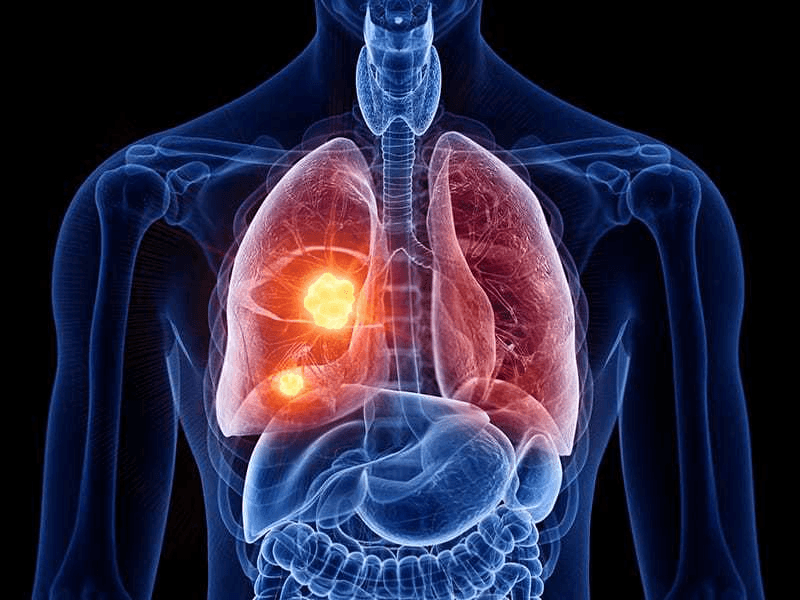

يُشير مرض السرطان إلى انتشار خارج عن السيطرة لخلايا غير طبيعية وقادرة على غزو الأنسجة الحية في الجسم، ويمكن أن ينتشر عبر الجسم عن طريق الدم أو الجهاز الليمفاوي، ومن الطبيعي وجود خلايا غير طبيعية في الجسم، لكن يتخلص الجسم منها باستمرار في الأشخاص الأصحاء بنفس طريقة استخراج السموم سواء عبر التعرق أو التبول وغيرها، كما أن مضادات الأكسدة تساعد في تنقية الجسم من أي أجسام غريبة، ولكن عندما تدخل عوامل قوية مثل التدخين والمواد الكيميائية فإن تلك الخلايا تخرج عن السيطرة، ويفقد الجسم قدرته على التخلص السريع منها.

لا يزال سرطان الرئة يقتل الرجال والنساء أكثر من أي نوع آخر من السرطان، ووفقًا لمنظمة الصحة العالمية فهو في المركز الثاني تبعًا للانتشار على مستوى العالم بعد سرطان الثدي، ولكنه الأول على مستوى التسبب في الوفاة، إذ يموت 9 من كل 10 أشخاص مصابين بسرطان الرئة والذي يعد كل من التدخين والتدخين السلبي السبب الأساسي فيه.

ويرتبط التدخين بالسرطان بشدة أكثر من أي عنصر آخر، فالسموم الموجودة في دخان السجائر تُضعف جهاز المناعة وتجعله أقل مقاومة أمام الخلايا السرطانية أو غير الطبيعية التي تنتشر في الجسم وتنمو بالتالي دون توقف أو رادع.

كما أن دخان التبغ يُتلف أو يغيِّر من طبيعة الحمض النووي وبهذا يُدمر "الدليل" الذي يحدد النمو الطبيعي للخلية ووظيفتها، ومع تدمير هذا الدليل فإن الخلية تخرج عن نطاق السيطرة في النمو وتزيد فرص تشكل كتل سرطانية.

ويمكن للتدخين أن يتسبب في أنواع مختلفة من السرطان بالإضافة إلى سرطان الرئة ومنها: